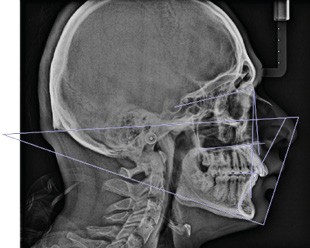

Examen radiologique

D’après l’analyse céphalométrique (fig. 10), le patient est en classe II squelettique (ANB = 7°) dans un contexte normodivergent (FMA = 22°). Les incisives maxillaires sont vestibulo-versées (I/F = 120°). Il en est de même pour les incisives mandibulaires (IMPA = 98°).